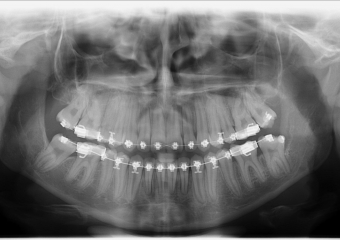

Rx Panorâmico, com os dentes em fase final de tracionamento - Clínica Cliniface

Rx Panorâmico, com os dentes em fase final de tracionamento